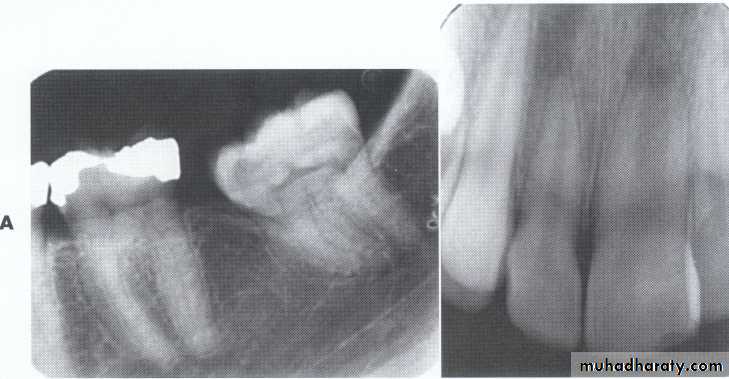

Impaction:

most often affects the mandibular 3rd molars &maxillary canines.

less commonly:

premolars

mandibular canines

second molars

CAUSES: due to obstruction from crowding.

occasionally, may be due to an abnormal eruption

path, presumably because of unusual orientation of

tooth germ.